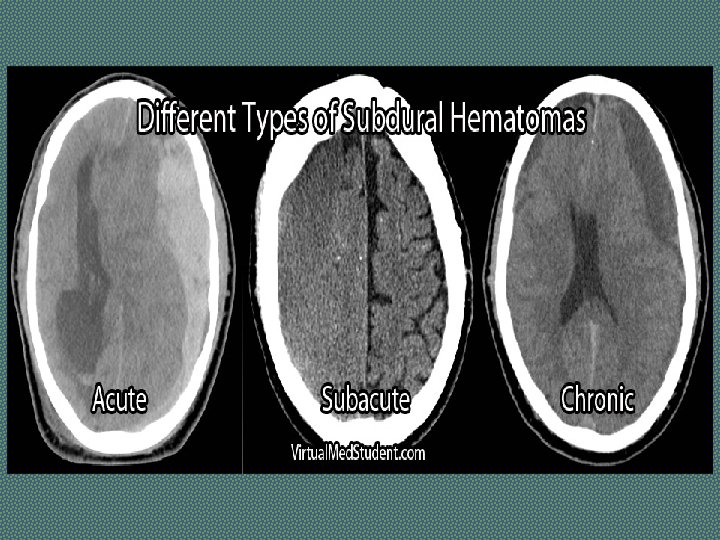

SPACE OCCUPYING LESION Lesion which occupy the cranial cavity and displace or destroy existing structures Causes: Tumour, Abscess, Hematoma, Tuberculomas Symptoms: H/O gradual onset of weakness developing over weeks to months. Headache and vomiting There may be H/O trauma (Hematoma) H/O waxing and waning of concious level (Subdural Hematoma) H/O fever and ear discharge suggest an abscess. Signs: In addition to motor deficit, following signs may be present: Bradycardia Fundoscopy……Papilledema Investigations: CT scan (with contrast), MRI

Investigations of Stroke Ø Brain Computed Tomography (CT) Scan Ø Magnetic resonance imaging (MRI) Ø Computed Tomography Arteriogram and Magnetic Resonance Arteriogram: Aneurysm, AV malformation Ø Carotid Ultrasound Ø ECG and Echocardiography Ø Lumber Puncture: Subarachnoid Hemorrhage